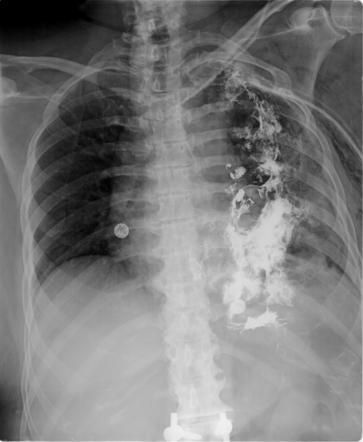

Boerhaave syndrome refers to rupture of esophagus secondary to forceful emesis. Alcoholism is one of the major risk factors. The condition is characterized by Mackler’s Triad: - Vomiting - Subcutaneous emphysema - Chest pain Reference: https://radiopaedia.org/articles/boerhaave-syndrome Image via: https://radiopaedia.org/articles/boerhaave-syndrome